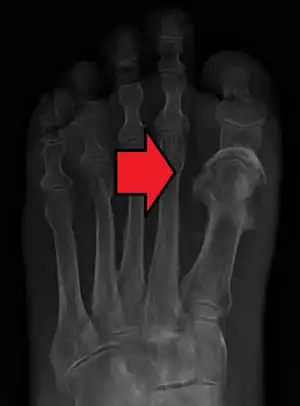

Osteomylitis of first toe